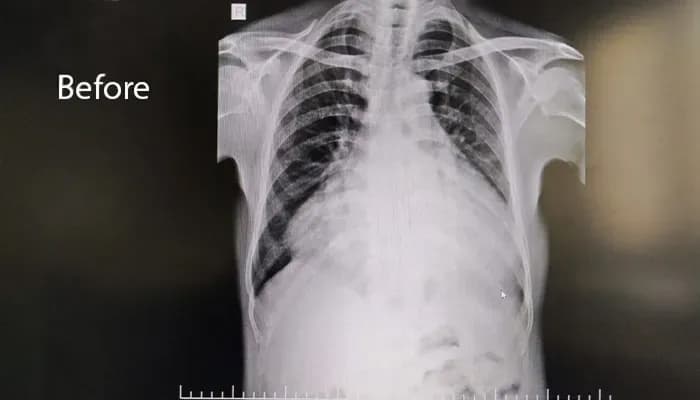

The patient presented with progressive breathlessness and intermittent chest discomfort, caused by a ruptured sinus of Valsalva aneurysm leading to acute left-to-right shunt, severe volume overload, and congestive cardiac failure.

- Cardiomegaly with preserved biventricular systolic function